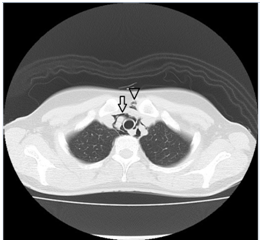

A previously healthy 28-year-old woman suddenly developed left chest pain while eating lunch, with no cough or vomiting. She visited my office because of persistent chest pain and anxiety. Her vital signs were stable on admission. She had not taken any medications recently, nor reported a habit of cigarette smoking. Physical examination revealed no aerodermectasia or abnormal chest sounds, including crunching heart sounds. The electrocardiogram (ECG) was normal. Chest radiographs showed air dissecting the left second arc protrusion Figure 1, black arrow and in the superior mediastinum Figure 1, black arrow head. Computed tomography (CT) of the chest also revealed air in the mediastinum Figure 2, white arrow, as well as aerodermectasia Figure 2, arrow head not detected in the radiographs, without pneumothorax or oesophageal rupture. An oesophagogram demonstrated no leakage in the mediastinum or pleural space. These findings confirmed a diagnosis of SPM. The patient’s chest pain improved gradually, and spontaneously resolved completely within 1 week with conservative management.

Figure 2 A chest CT showing intramediastinal air (white arrow) and aerodermectasia (white arrow head) without pneumothorax.